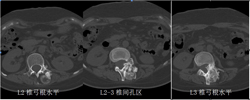

图3-1,CT矢状面和冠状面重建,显示病变为成骨性,病变内有点状钙化。

图3-2,CT横断面显示病变累及L2-L3水平椎骨。